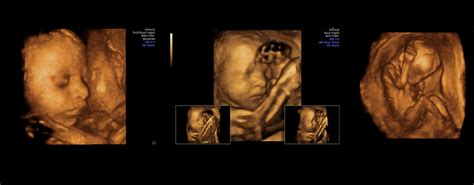

80% din examinarea ecografică propriu-zisă se realizează în modul 2D, însă ecograful cu capabilități 3D/4D sporește calitatea imaginii 2D analizate de medic cu până la 40%. Modulul de examinare în 3D/4D este folosit la finalul detalierii morfologice. Softul 3D/4D ne oferă imagini tridimensionale cu fătul în timp real, ce pot fi oferite pacientei pe CD.

Ecografia 3D/4D în morfologia fetală

Dr. Cristian Nicolae, medic primar Radiologie și Imagistică Medicală explică rolul Ecografiei de Sarcină 3D/4D, ca element complementar Ecografiei de Sarcină 2D. Mămicile trebuie să știe că softul 3D/4D crește cu până la 40% performanța modulului 2D, dar modulul 2D rămâne singura modalitate de analiză a dezvoltării anatomice a fătului.

- ROL EMOȚIONAL: „Ecografia 3D/4D reprezintă un beneficiu atunci când se dorește identificarea anumitor detalii și atunci când părinții sunt nerăbdători să-și vadă copilul din burtică și să-i analizeze trăsăturile! Aceasta creează un efect video live, similar unui film, cu bebelușul din burtica mamei și este o modalitate de apropiere a părinților de viitorul lor copil. Mai ales că, imaginea obținută prin examinarea 3D/4D de la 32-34 de săptămâni de sarcină este identică cu cea bebelușului pe care mama îl ia în brațe după naștere.”

- ROL EDUCATIV: „Această examinare permite evidențierea și înțelegerea de către părinți a eventualelor malformații ale fătului - membre, coloană vertebrală, față, craniu. Ele pot fi mult mai ușor arătate și explicate părinților. Ecografia 3D/4D nu constituie o metodă de diagnostic a problemelor de sănătate ale copilului, însă poate contribui cu informații suplimentare privind o anormalitate deja constatată în timpul ecografiei 2D.”